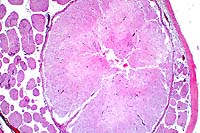

20x

obj

- Case 18-3. Lung. There is diffuse bronchiolar epithelial

necrosis with scattered eosinophilic intranuclear inclusions

(arrowhead), and several syncytial cells in various stages of

degeneration. The bronchial lumen is filled with cell debris

and the pulmonary interstitium is expanded by edema, a mixed

cellular infiltrate, and cellular debris.

- AFIP Diagnosis: Lung: Pneumonia, broncho-interstitial,

necrotizing, acute, diffuse, severe, with syncytial cells, eosinophilic

intranuclear inclusion bodies, edema, hemorrhage, and fibrin,

breed unspecified, equine, etiology consistent with equine herpesvirus

type I.

- Contributor's Diagnosis and Comments: Multifocal necrotizing

bronchopneumonia with eosinophilic intranuclear inclusion bodies.

Etiology : Equine herpesvirus type I.

This is a good example of the lung lesions caused by equine herpesvirus.

There is diffuse congestion with interlobular and subpleural

edema. There are multiple foci of necrosis and hemorrhage in

the pulmonary parenchyma. Cells surrounding the necrotic foci

contain small eosinophilic intranuclear inclusion bodies. Necrosis

of bronchial and bronchiolar epithelium is also present, with

cellular debris in the lumens, and intranuclear inclusions are

present in cells near the necrotic areas. Focal necrosis and

intranuclear inclusions were also present in the liver, spleen

and thymus.